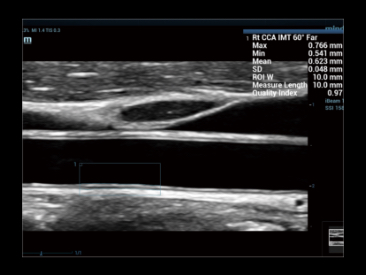

Wyra?niejszy obraz umo?liwiaj?cy pewn? diagnoz?

iClear+ jest oparty na wydajnej technologii przetwarzania ZST+ i zapewnia lepszy stosunek sygna?u do szumu (SNR) oraz mniej zak?óceń, co pozwala na lepsz? wizualizacj?.

Przypadek kliniczny z wykorzystaniem technologii iClear: staw barkowy